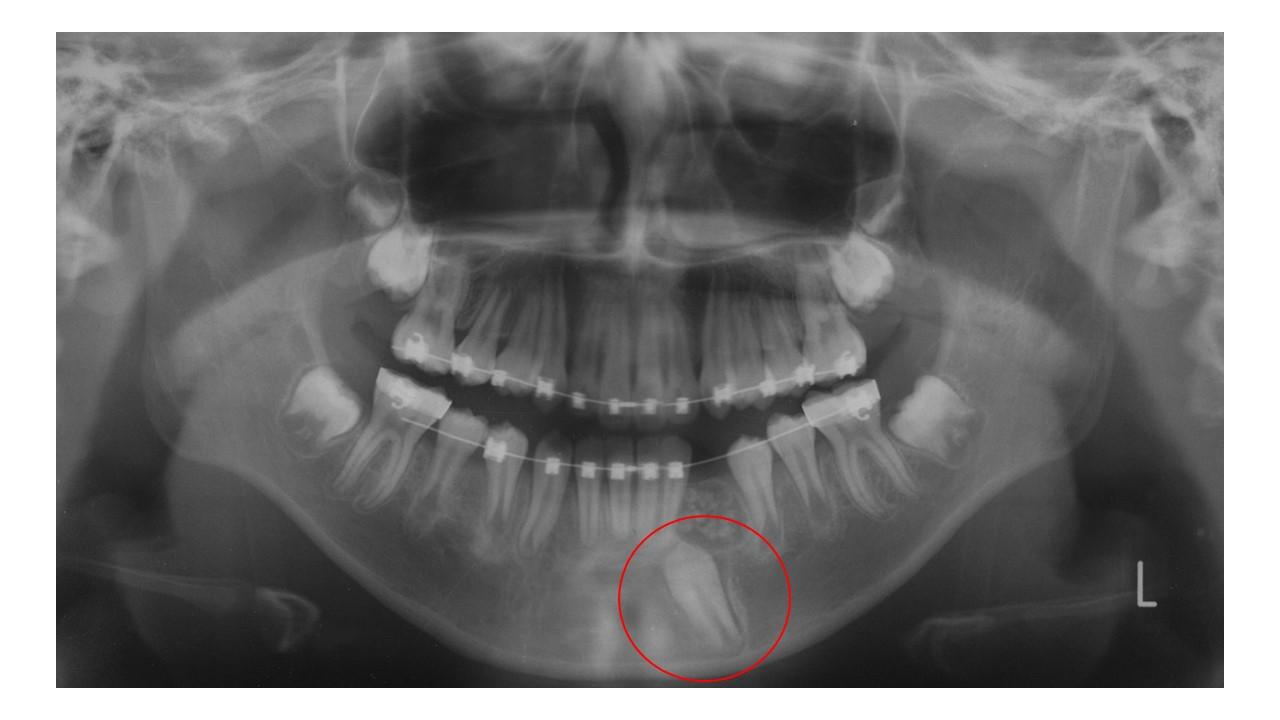

Gömülü diş tedavisi, çene kemiği içinde sürmeyen veya yanlış konumlanan dişlerin ağız sağlığını koruyacak şekilde değerlendirilmesini ve uygun tedavi yöntemlerinin planlanmasını amaçlar; böylece olası ağrı, enfeksiyon ve komşu dişlere zarar verme risklerinin önüne geçilmesi hedeflenir.